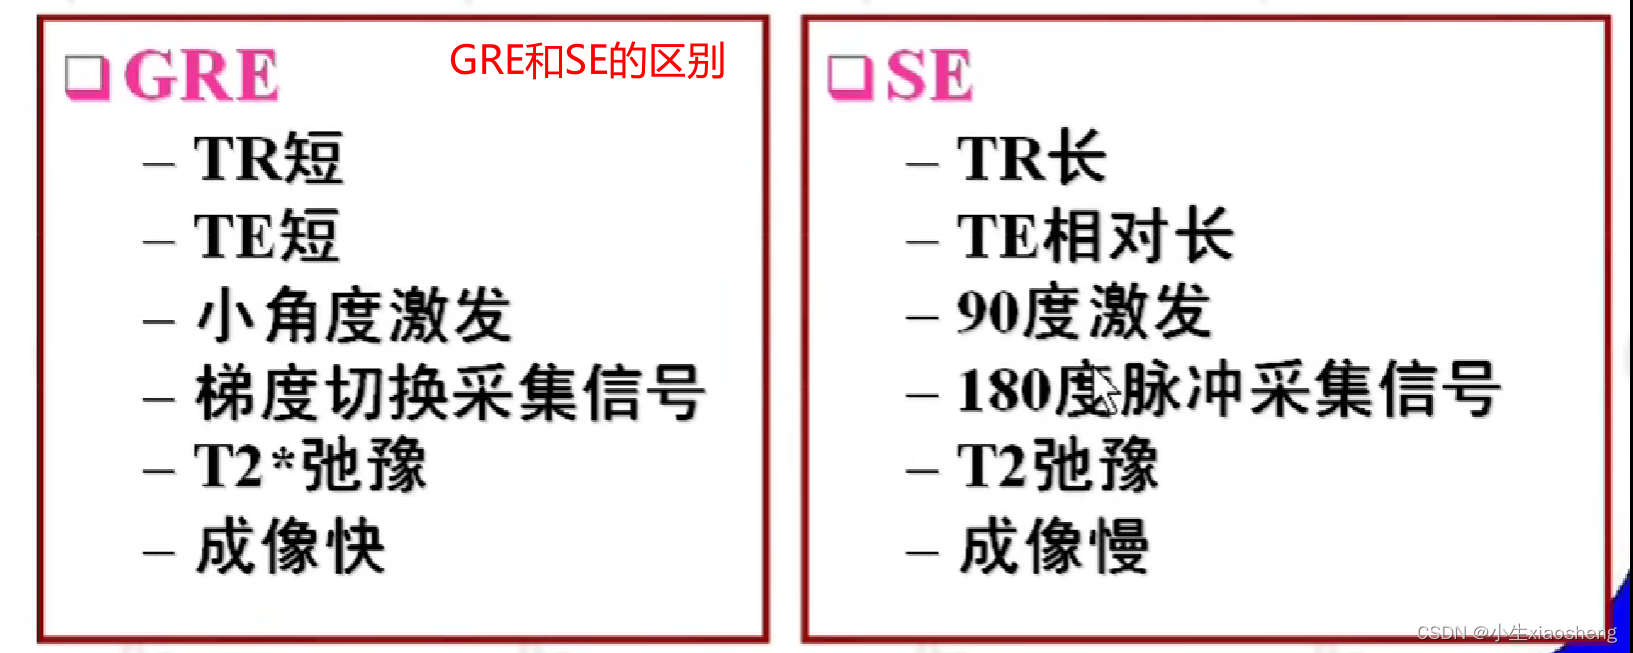

五、梯度回波类序列

GRE就是梯度回波